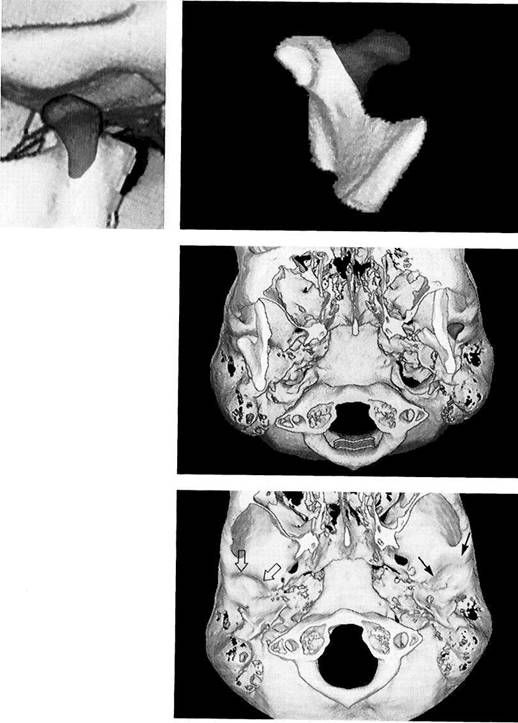

Three-dimensional repre­sentation of a temporo­mandibular joint

A three-dimensional image of the joint can be reconstructed from CT measurement data. Further detail can be seen by separating the condyle from the fossa. Special software (Denta-CT) is available for the orofacial region and is designed especially for three-dimensional imaging of the alveolar processes (Abrahams and Kalyanpur 1995).

Three-dimensional representation of the fossa

An inferior view of the articular fossa from Figure 399 is shown. This view permits scrutiny of the condylar path and the articular em­inence. The image can be rotated on the monitor so that the mor­phology and inclination of the joint pathway can be calculated. This de­termination has no clinical rele­vance, however. In edentulous pa­tients the fossa lies more anterior than it does in patients with teeth. Its sagittal position depends on how long the patient has been edentulous (Raustia et al. 1998).

Three-dimensional repre­sentation of the condyle

This separate image of the condyle allows inspection of the joint surface. This type of image is only important for primary temporo­mandibular joint diseases, how­ever. Changes in the articular sur­faces due to dysfunction can be adequately diagnosed clinically and do not require three-dimensional imaging, as the radiographic find­ings would not change the treat­ment.

Condition 3 years after fracture of the neck of the left condyle

Three-dimensional image recon­structed from CT scans of the condyle of a 14-year-old patient fol­lowing fracture of the left condylar process of the mandible. The isolat­ed image of the condyle reveals that the anteromedially displaced fragment has healed in the wrong position and a "new" condyle (red) has formed lateral to it.

Left: Reconstructed left joint in a lateral view showing the new for­mation of a condylar process (red).

Inferior view

for side-by-side comparison

This caudal view clearly shows the abnormal shape of the condyle in the left joint. The healed dislocated medial fragment and the remodel­ing in the lateral part (red) have cre­ated a V-shaped condyle. In spite of the absence of physiological condy­lar form, the post-traumatic open bite found in this type of case can be closed through muscular adap­tation during functional orthodon­tic treatment (Kahl et al. 1995, Choi

Changes in the joint pathway following fracture of the neck of the condyle

Digital subtraction of the condyles allows inspection and comparison of the two fossae. The V-shaped left condyle has led to flattening of the articular protuberance in the left joint (arrows). The right joint ex­hibits normal contours (outlined ar­rows). The joint pathway may be flattened by both a reduction of the eminence and apposition of bone on the roof of the fossa (Sahm and Witt 1989).

Goldenhar syndrome

405 Frontal view

Three-dimensional reconstruction of the cranium and facial skeleton of an 8-year-old boy. Because of hypoplasia of the left ascending ramus the mandible has deviated to the left and the maxilla has under­gone secondary adaptive changes. The more pronounced the adaptive changes, the more important it is to institute functional therapy in addition to surgical correction (Behniaetal. 1997).

Right temporomandibular joint

Three-dimensional reconstruction of the unaffected right side. The re­lationship between the ascending ramus and the condylar process is almost normal. The condyle shows a slight flattening inconsistent with the patient's age. The external au­ditory meatus and glenoid fossa show no deviation from the norm. Even though it is theoretically pos­sible to represent the muscles of mastication in a CT, MRI is to be preferred for evaluating muscular changes.

407 Left temporomandibular joint

On the left side, the mandible is no­ticeably underdeveloped. This af­fects the height of both the body of the mandible and the ascending ramus. In addition, both the condy­lar process and the articular emi­nence are hypoplastic. The osseous external auditory meatus is obliter­ated. While planning the surgical operation for distraction osteogen­esis, the shapes of the ascending ramus and the condylar process are especially important for determin­ing the exact distraction vector.